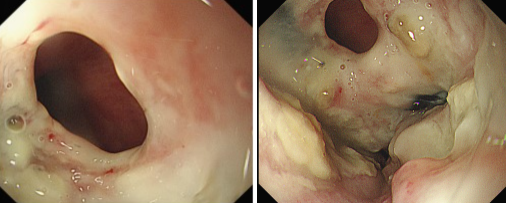

品質國文 | 重獲進食希望——內鏡下食管覆膜支架植入手術

張大爺近期突然遭遇進食困難,還頻繁出現(xiàn)進食嗆咳的狀況。緊急檢查后,確診為食管惡性腫瘤,同時并發(fā)食管氣管瘺,而且因食物誤吸引發(fā)了肺部感染。由于瘺口的存在,食物不斷進入氣道,致使嗆咳加劇、感染惡化,這不僅嚴重降低了張大爺?shù)纳钯|量,更對其生命構成了極大威脅。 閱讀量:1248